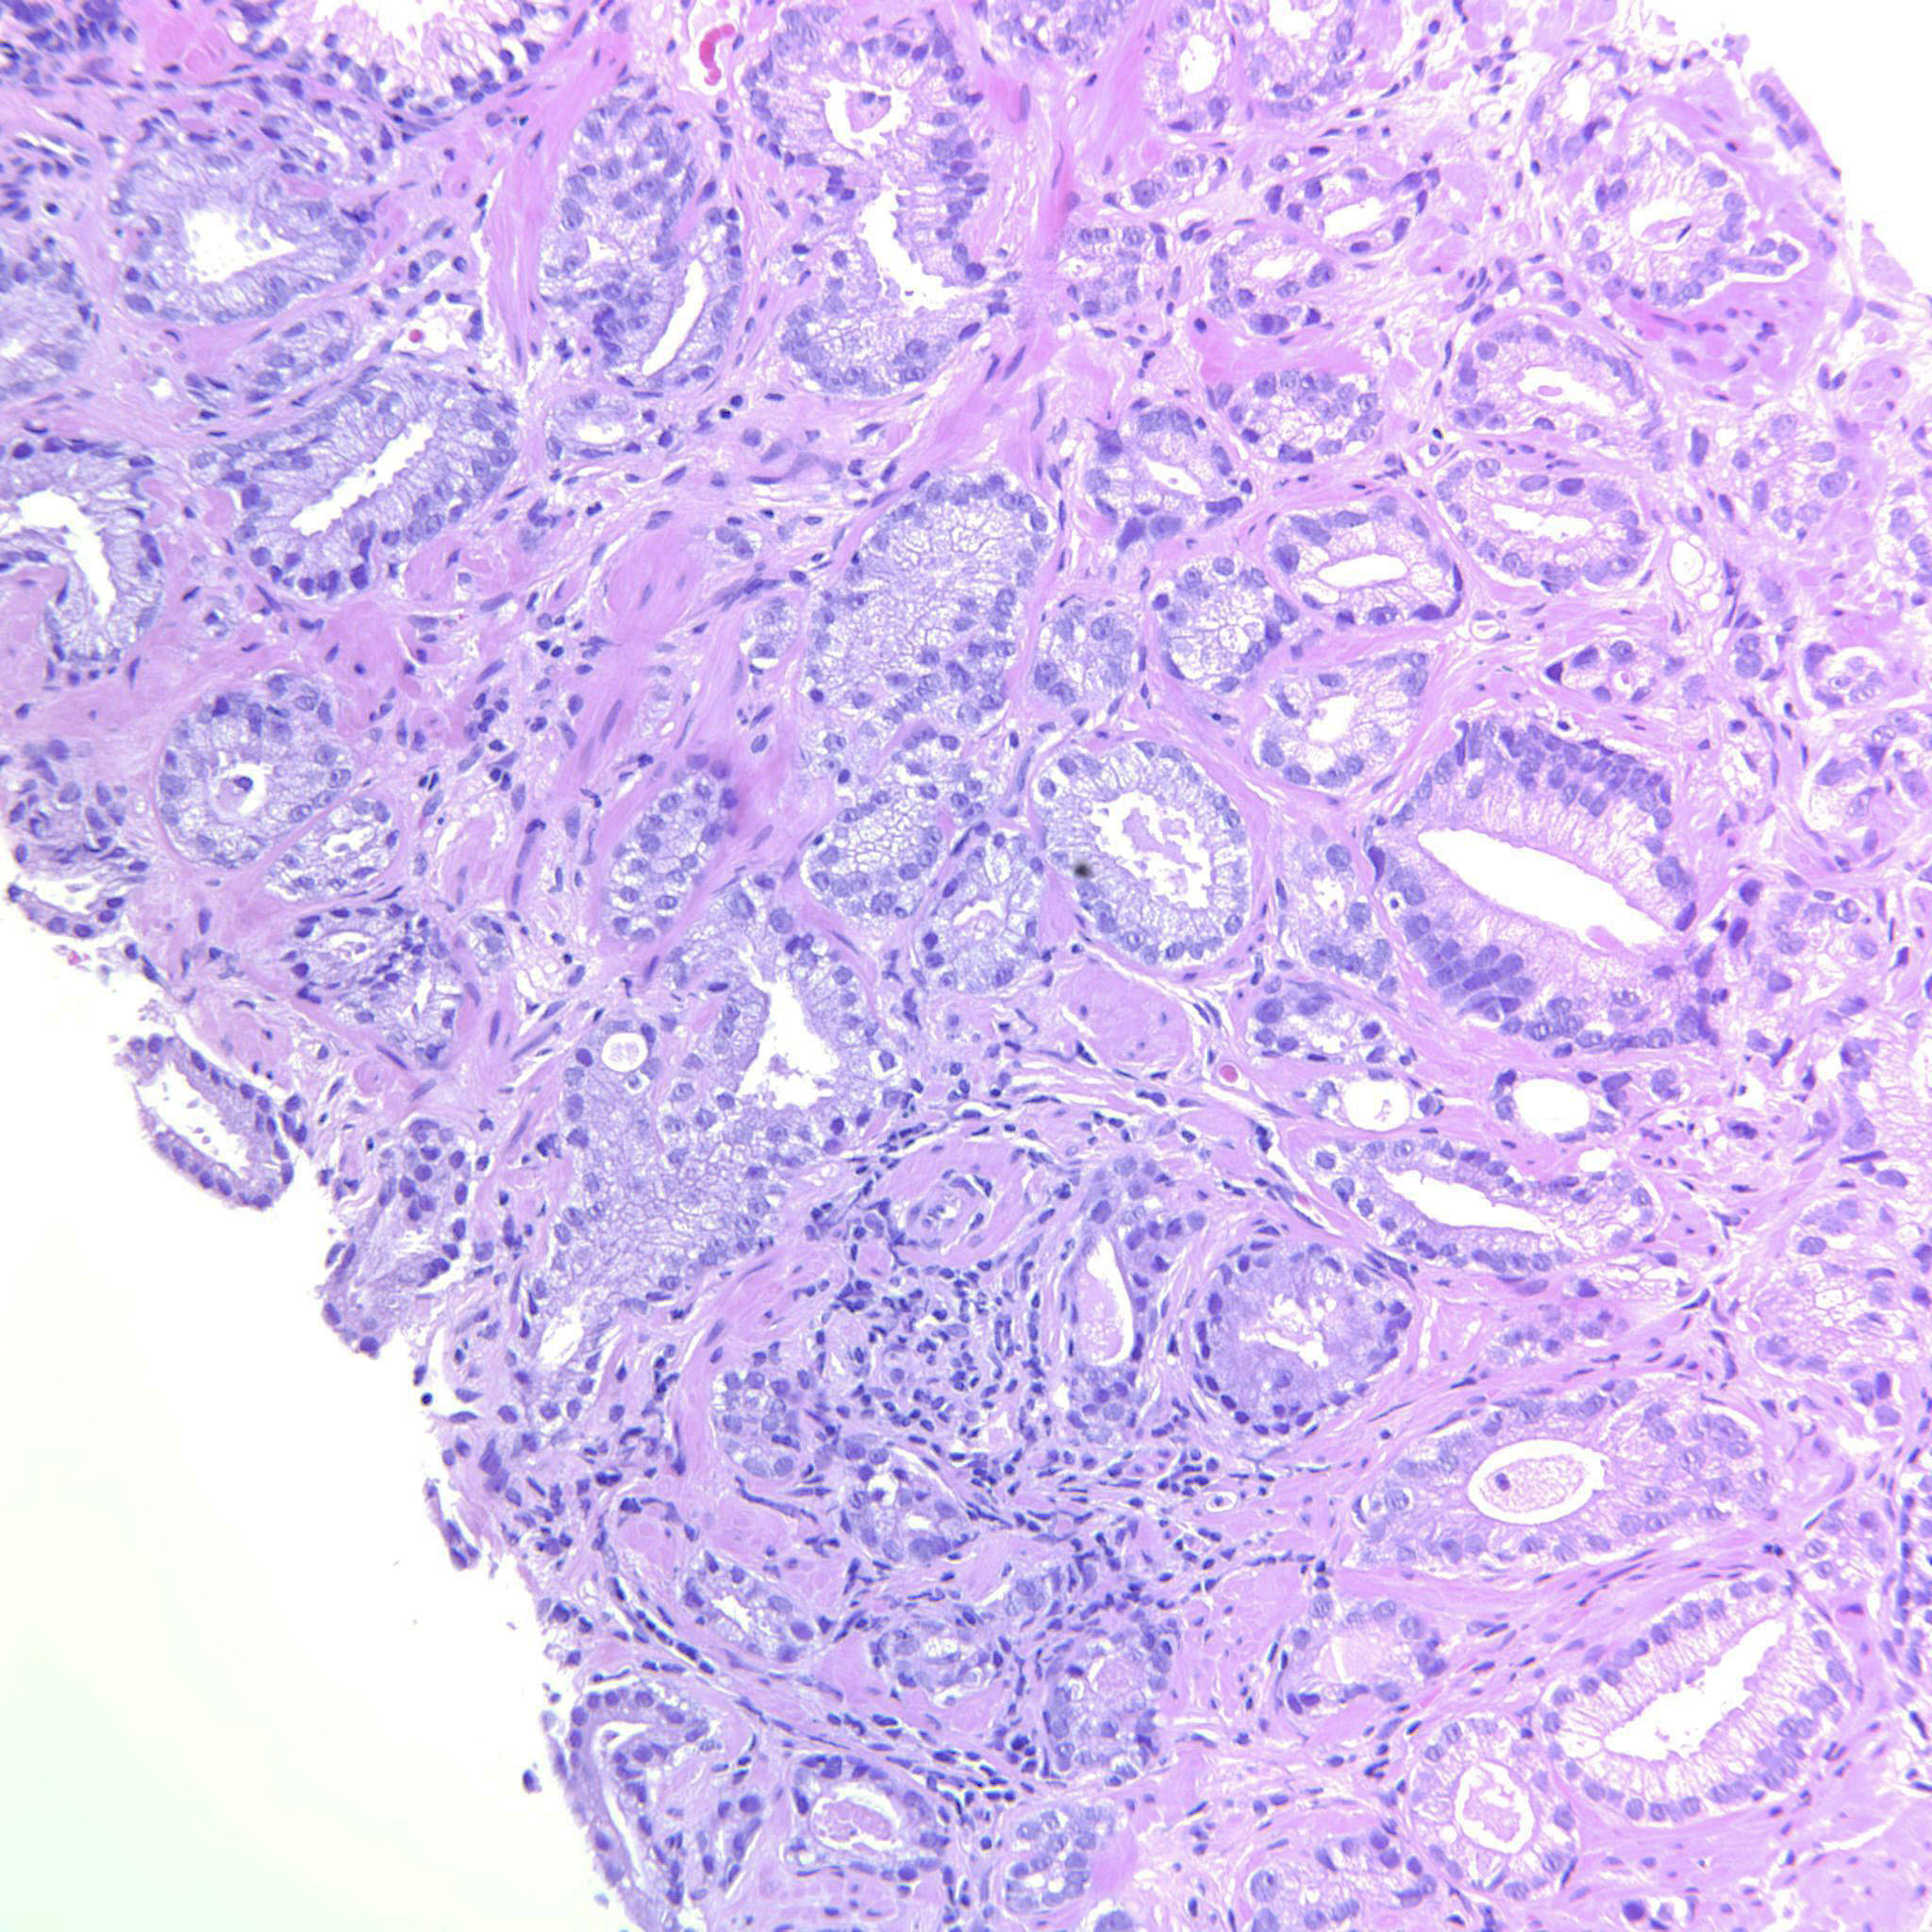

Consensus grade: GS 3+4=7 (ISUP 2)

Case description (by case creator):

Scattered poorly formed glands throughout the material.